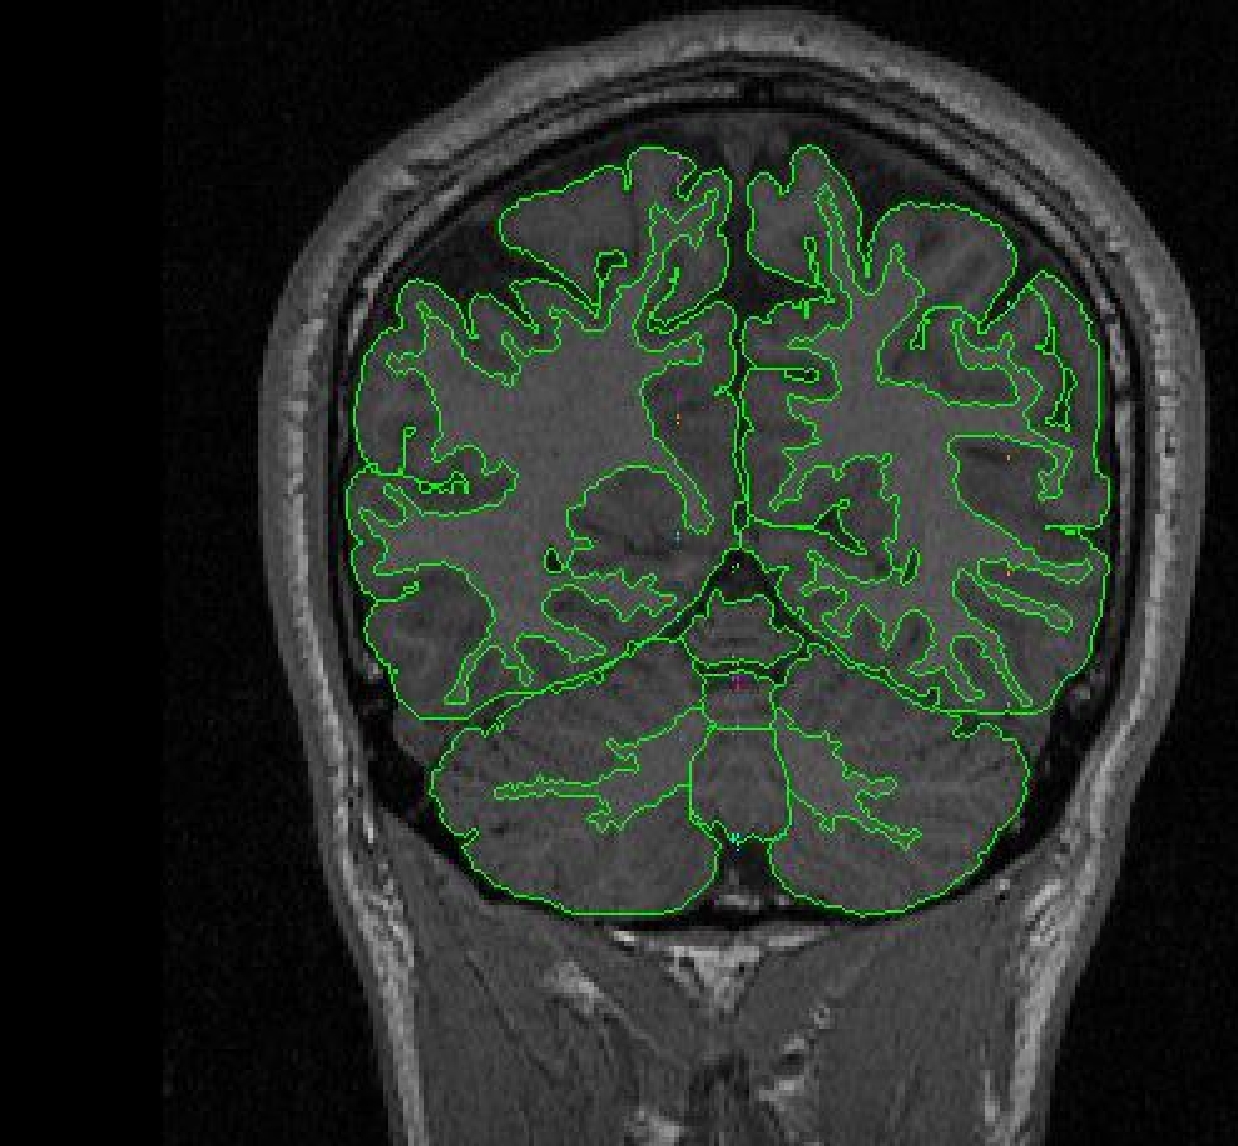

Part IIb - Cerebellum hemispheres

Use the contour function to define the exterior of the cerebellum. Use the draw function to exclude any non-brain tissue, as well as to draw in the midline. Extract the right cerebellum hemisphere exterior and left cerebellum hemisphere exterior separately.

Using the projection lines and alternate views is important to determining

the cerebellar borders. One difficult area is the

extreme of the cerebellum, as well as the sinuses that run along the tips

of the lateral cerebellum wings in the cerebellar contour. These sinuses

will be superior to the cerebellum and may be mistaken for cerebellum.

Labeling

The vermal lobules are labeled as l-V, Vl-Vll and Vlll-X. The cerebellar hemispheres

are labeled as right and left cerebellar hemispheres and the white matter is

labeled cerebellar white matter.